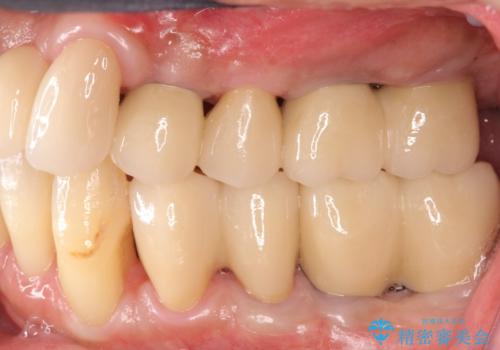

長期間にわたる治療後、歯に対する意識も大きく変わりプラークコントロールも非常に良くなりました。

数ヶ月に一度のチェックをしっかりと行い、ブリッジ・インプラントが長期間使用できるようメンテンスを行っていきます。